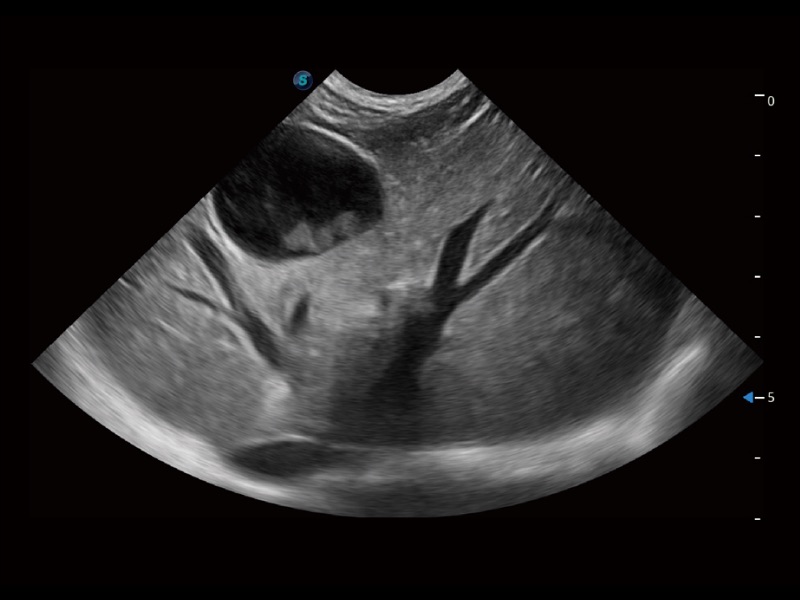

大型犬、马科、农场动物及大型异宠动物

ProPet 70专为动物医生设计,对不同的动物体型和生理结构作出了针对性的优化。通过动物影像专用软件,可满足个性化的应用需求,帮助动物医生获得更精确的诊断数据。

为精细结构及组织边缘提供高清晰度的图像和更大的成像视野。帮助减轻医生的用眼疲劳,快速精准获得测量的数据。

提供解剖示意图、标准超声图像、扫查手法图和操作者实时检查图像,指导操作者进行标准切面的正确扫查。